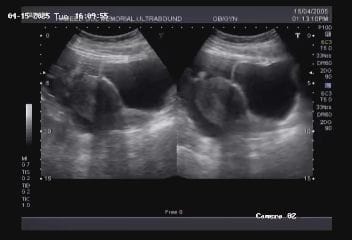

Our institutue provides high-quality ultrasound imagies for various diagnostic applications. these images serve as essential tools for accurate diagnostic and treatment planning.

doppler imagies

Doppler ultrasound provides critical information about the blood flow within vessels and tissues, enabling precise diagnosis of vascular conditions.